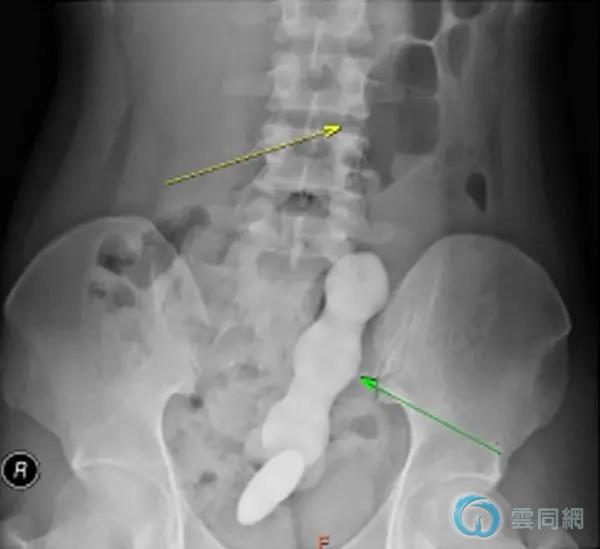

“腹部正侧位位片显示盆腔直肠乙状结肠内可见一高密度不规则物体,长度约20cm,直径最宽处约4.2cm,致密物上端肠管扩张,积气明显。”代建德立即赶赴科室,充分评估患者病情,并与科室医务人员进行反复讨论。